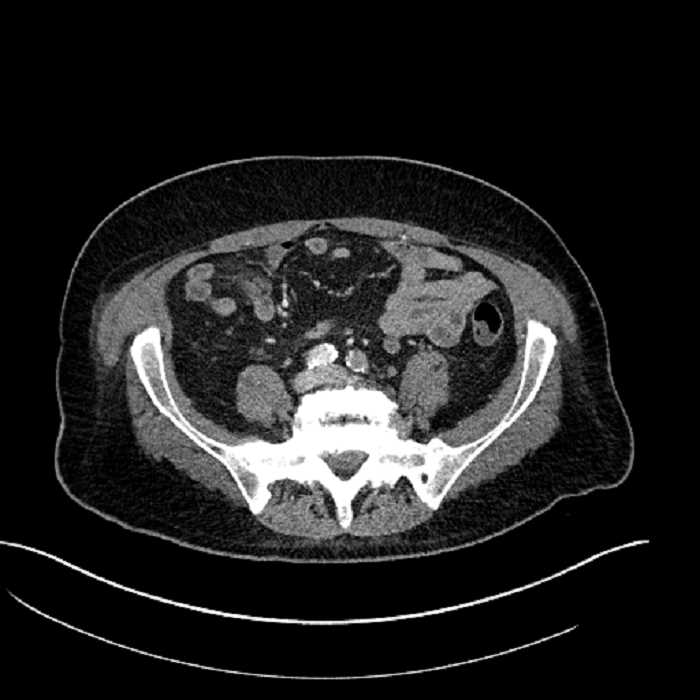

Age: 63

Sex: Male

Indication: Abdominal pain

• Mild mural thickening of a segment of the sigmoid colon with adjacent fat stranding and a 1.5 cm fluid and gas collection along the tip of an inflamed diverticulum

• Loss of the normal fat plane between this collection and adjacent loops of small bowel, which demonstrate mural thickening

• No bowel obstruction

Acute sigmoid diverticulitis complicated by a small contained perforation and a large abscess in the right hepatic lobe. Additional small subcapsular abscesses along the anterior margin of the left hepatic lobe.

Additionally, loss of the normal fat plane between the peridiverticular collection and adjacent thickened loops of small bowel raises the potential for an enterocolonic fistula.

Hepatic abscess showing the double target sign with low density internally surrounded by a thin inner enhancing rim (red arrow) and ill-defined outer low density rim (yellow arrow). Blue arrow indicates an internal septation. Red arrows: additional smaller subcapsular abscesses. Red arrow: focal contained perforation associated with diverticulitis.